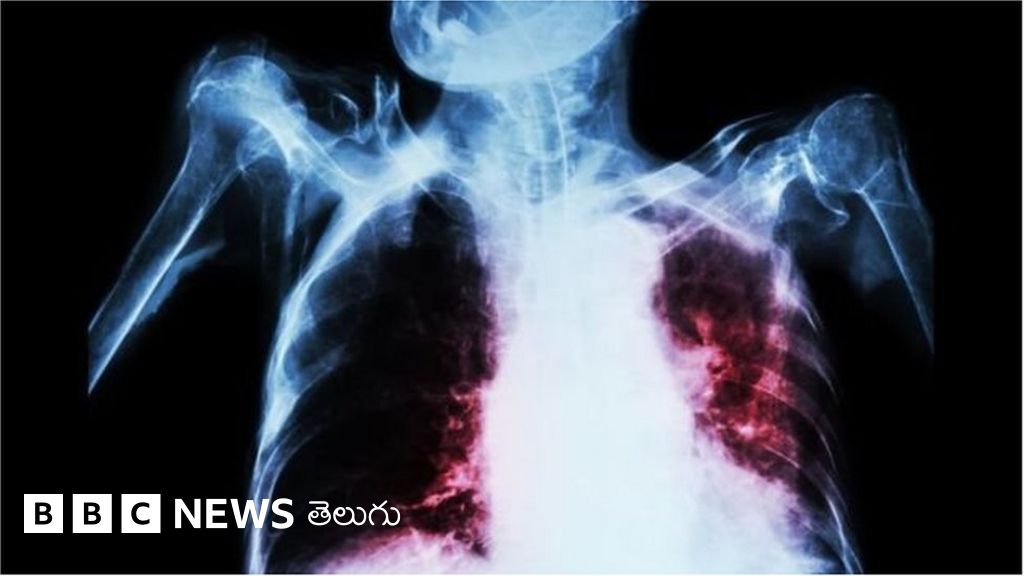

ట్యూబర్ క్యులాసిస్(క్షయ) చికిత్సలో విప్లవాత్మక మార్పులను తీసుకురాగల వ్యాక్సిన్ను పరిశోధకులు ఆవిష్కరించారు.

ఏటా ప్రపంచవ్యాప్తంగా 15 లక్షల మంది మరణానికి కారణమవుతున్న వ్యాధి నుంచి ఇది రక్షణ కల్పిస్తుందని ఆశిస్తున్నారు.

ఒకరి నుంచి ఒకరి సులభంగా సోకే ఈ వ్యాధి బ్యాక్టీరియా వల్ల వస్తుంది. ప్రస్తుతం వినియోగంలో ఉన్న బీసీజీ జబ్ పెద్దగా ప్రభావవంతంగా లేదు.